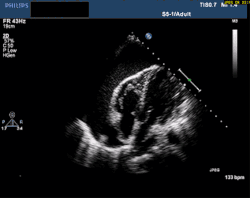

Echocardiogram of cardiac tamponade. Fluid surrounding the heart impairs proper filling. This swinging of the heart causes electrical alternans seen on EKG.

A pericardial effusion is fluid in the pericardial sac. When large enough, the pressure compresses the heart. This causes shock by preventing the heart from filling with blood. This is called cardiac tamponade. The chambers of the heart can collapse from this pressure. The right heart has thinner walls and collapses more easily. With less venous return, cardiac output decreases. The lack of blood flow to vital organs can cause death.[19]

Whether an effusion causes tamponade depends on the amount of fluid and how long it took to accumulate. When fluid collects slowly, the pericardium can stretch. Thus, a chronic effusion can be as large as 1 liter.[20] Acute effusions can cause tamponade when small because the tissue does not have time to stretch.[21]

At the bedside, point-of-care echocardiography should be used.[22] This is non-invasive and can help diagnose the four types of shock.[24] Echocardiography can look for ventricular dysfunction, effusions, or valve dysfunction.[3][25] Measurement of the vena cava during the breathing cycle can help assess volume status.[22][24] A point-of-care echocardiogram can also assess for causes of obstructive shock. The vena cava would be dilated due to the obstruction. In pulmonary embolism, the right ventricle will be dilated. Other findings include paradoxical septal motion or clots in the right heart or pulmonary artery. Echocardiography can assess for pericardial effusion. In tamponade, collapse of the right atrium and ventricle would be seen due to pressure in the pericardial sac.[24]